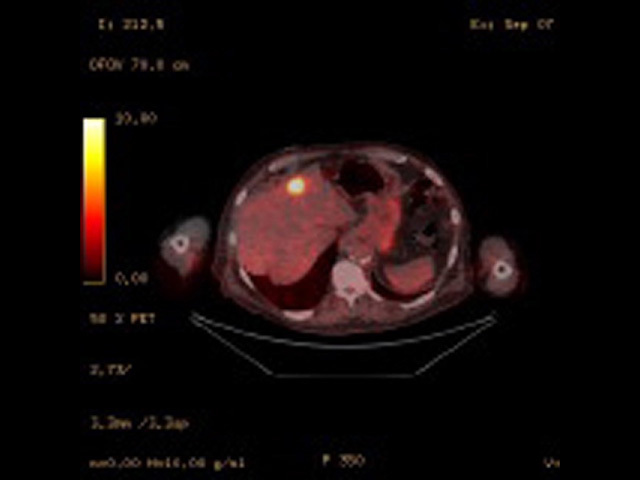

Fused PET/CT image of liver metastasis

Basic radiological investigations such as chest x-ray (CXR) can detect occult metastatic melanoma, but their two-dimensional soft-tissue views are limited [5]. Thus many patients will be referred for CT, positron emission tomography-CT (PET-CT), ultrasound imaging, and MRI scans.

CT and PET-CT scans are commonly used in staging and surveillance of many solid malignancies.

Multiple studies have evaluated the overall accuracy of PET-CT staging and surveillance.